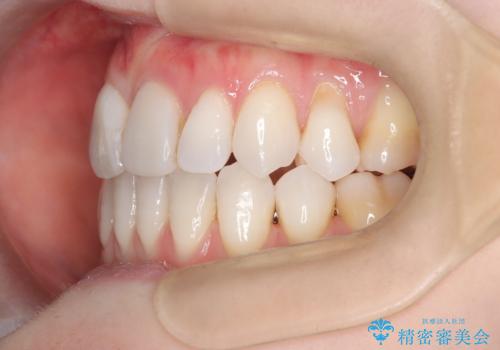

- 患者様は、歯並びの乱れ(叢生)を整えたいが、前歯の突出感は気にならないとのことで来院されました。診察の結果、全体的な歯列のスペース不足により抜歯が必要と判断。しかし、前歯を大きく下げる必要はなかったため、小臼歯の中でも5番(第二小臼歯)を抜歯する治療計画を立てました。装置は、上顎が舌側(リンガル)、下顎が表側(審美ワイヤー)のハーフリンガル矯正を採用し、目立ちにくさと効率的な歯の移動を両立しました。

抜歯によって歯を並べるためのスペースを確保。その後、ハーフリンガル矯正を用いて、上顎は舌側から、下顎は目立ちにくいワイヤーで歯を誘導し、歯列全体を整えました。治療期間を通じて、噛み合わせのバランスも改善し、機能的にも審美的にも理想的な仕上がりとなりました。患者様からは「目立たずに矯正でき、きれいな歯並びになって嬉しい」とご満足いただきました。